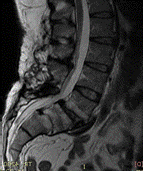

Ryc.2. a,b) MRI kręgosłupa lędźwiowego 72- letniego chorego z przewlekłymi objawami chromania neurogennego – nie jest w stanie przejść bez przystanku więcej niż 100m. Widoczne krytyczne zwężenie kanału kręgowego na poziomie L4-L5 widoczne na wszystkich skanach. C) dla porównania MRI kręgosłupa innego chorego bez stenozy. Zielone linie oznaczają poziom, na którym widoczny jest skan poprzeczny na zdjęciu obok.